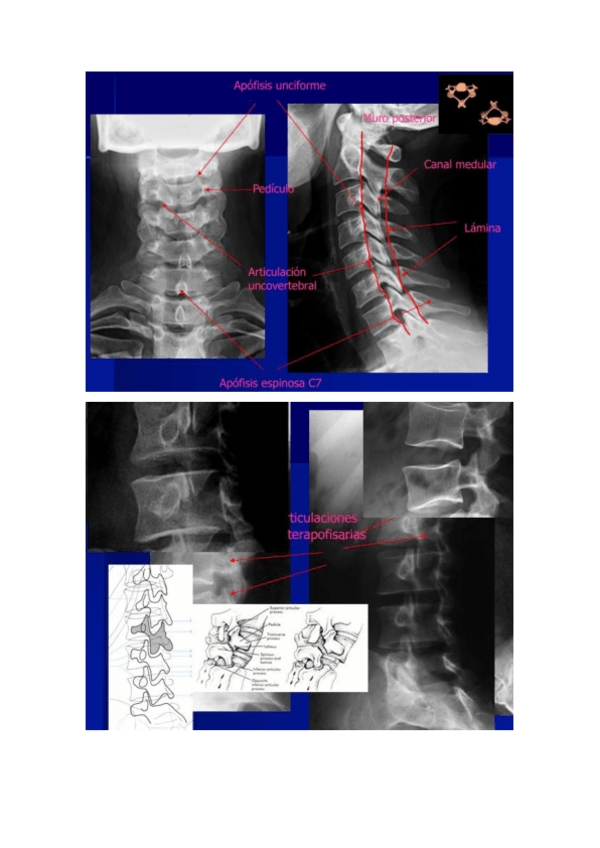

TALLER01Anato-Radiologica-Cervical-i-Mediasti.pdf